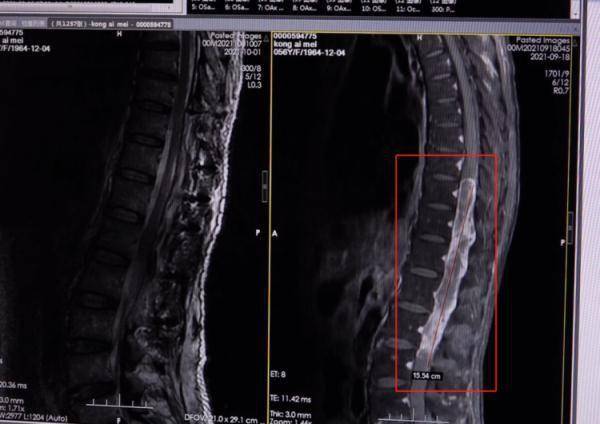

文章图片

而经过细致检查

医生发现王阿姨椎管内五个节段

有明显占位

诊断她患有神经鞘瘤

神经鞘瘤是良性肿瘤

一般只有蚕豆或者鸡肾大小

但王阿姨体内的肿瘤

竟长达13公分